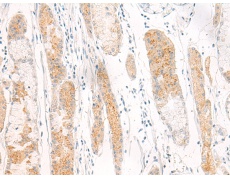

IHC positive control: |

Human gastric cancer |

IHC Recommend dilution: |

30-150 |